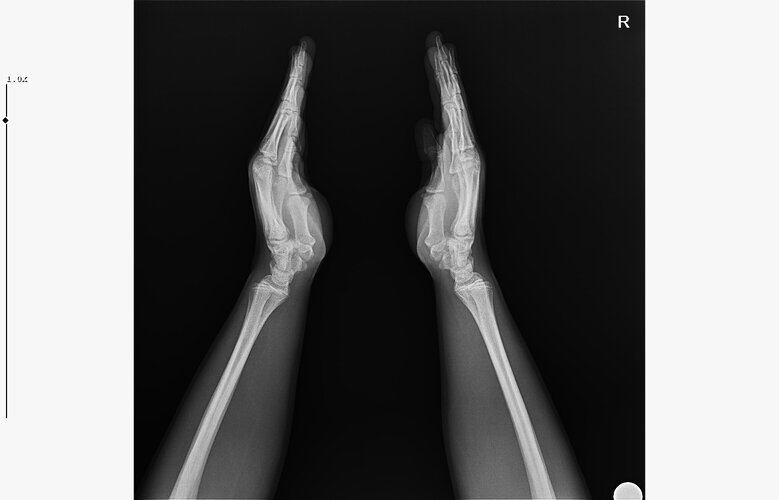

doktor bi sik bilmiyodur büyük ihtimalle plakları buraya at biz bakak

röntgeni atar mısın?

• WhatsApp Image 2026-01-07 at 00.31.08.jpeg

WhatsApp Image 2026-01-07 at 00.31.08.jpeg

138.6 KB · Views: 0

bilmiyo zaten,ki el plakları boy ile neredeyse hicbirsey göstermiyo bile ama tr de hangi doktora gidersen git %95inden fazlası el plağına bakcak ona göre yorum yapcak

bilmiyorum nasıl eğitim alıyorlar da ya eskimiş yada mantık kurma yetenekleri yok

kemik yaşın 15 gibi 15'e çok yakın

anne baba boyun ve yaşını bilmiyorum sadece bu bilgilerle 171-175 arası diye tahmin ediyorum röntgen ile.

normalde anne babana göre 171-176 olman gerek zaten. kemik yaşın ve şuanki boyun ile yapılacak tahmin anne baban ile yapılabilecek tahminle nerdeyse birebir aynı yani büyük ihtimal o civarlar olursun bence